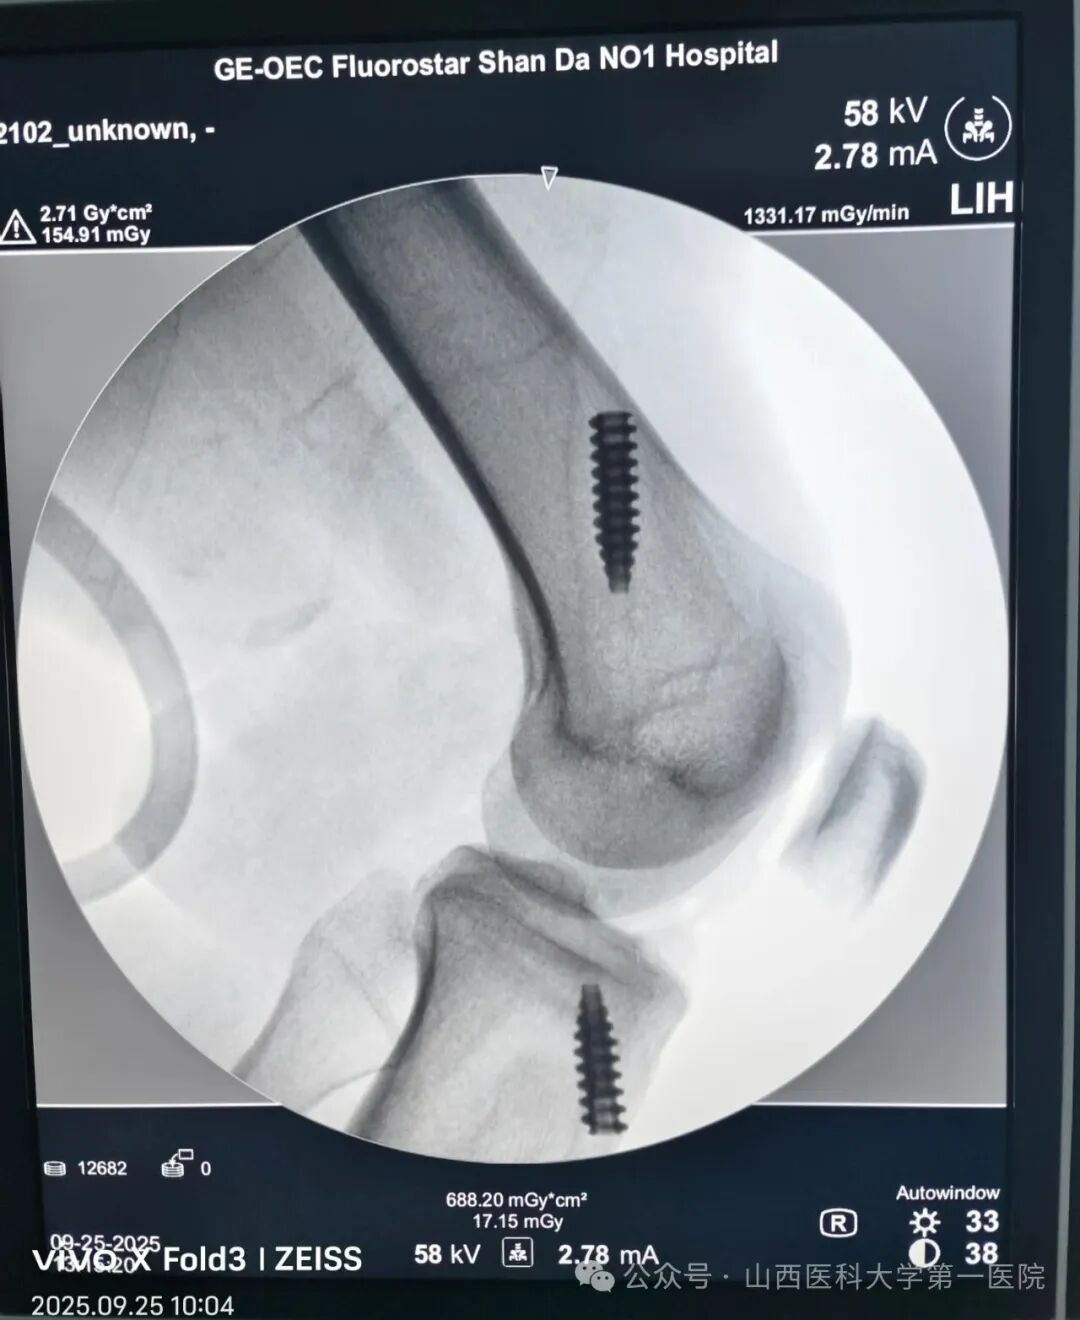

9月25日早7:30,一飞冲天游戏攻略站 日间手术中心收治了一位膝关节前交叉韧带损伤患者,经骨科运动医学韩晓强主任医师和付永良主治医师的精准评估和诊断,决定采用日间手术模式为其进行手术和康复,这也是日间手术中心收治的第一例膝关节人工韧带前交叉重建手术。

在完善术前检查和麻醉评估后,医生开始实施手术,术中采用人工韧带对其损伤的交叉韧带进行重建(人工韧带的强度约是自体韧带的3.2倍),术后即可开始康复锻炼,有利于肌肉和关节功能的尽早康复。手术历时1小时40分钟,患者术后2小时饮水、进食并开始踝泵运动,26日早7:00下床活动,经评估于上午9点顺利出院。这是骨科运动医学专业与日间手术中心的又一次完美合作,再度扩展了日间手术范畴,提升了日间手术的病种质量。